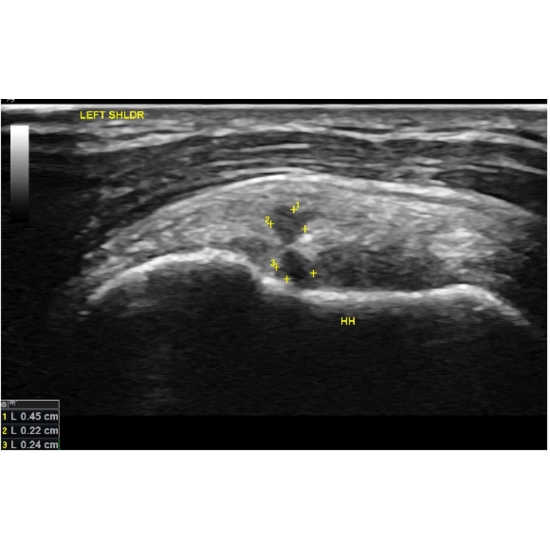

| Batter Up: Lr-prp For A Baseball Player With Ehlers-danlos Syndrome - A Case Report - Page #3 | |||